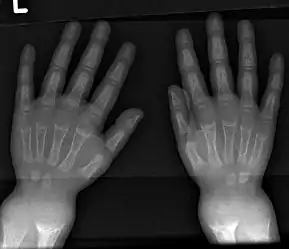

An X-ray or radiograph of an advanced patient with rickets tends to present in a classic way: the bowed legs (outward curve of long bone of the legs) and a deformed chest. Changes in the skull also occur causing a distinctive "square headed" appearance known as "caput quadratum".[14] These deformities persist into adult life if not treated. Long-term consequences include permanent curvatures or disfiguration of the long bones, and a curved back.[15]

- Radiography typically show widening of the zones of provisional calcification of the metaphyses secondary to unmineralized osteoid. Cupping, fraying, and splaying of metaphyses typically appears with growth and continued weight bearing.[41] These changes are seen predominantly at sites of rapid growth, including the proximal humerus, distal radius, distal femur and both the proximal and the distal tibia. Therefore, a skeletal survey for rickets can be accomplished with anteroposterior radiographs of the knees, wrists, and ankles.[41]